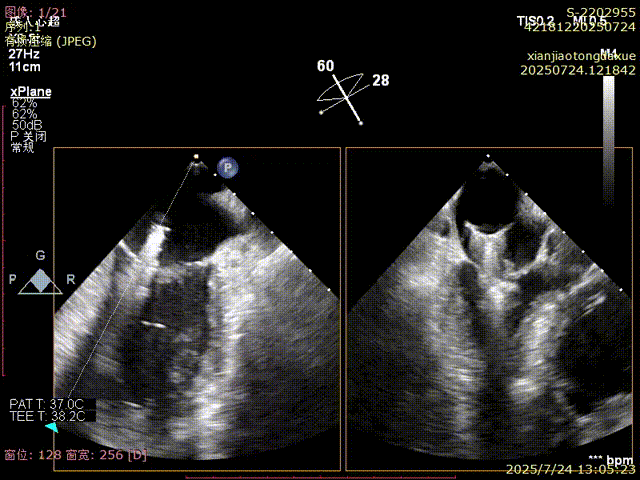

影像评估提示病变位于二尖瓣三区交界,瓣膜结构复杂,患者低氧血症,无法耐受体外循环,传统外科修复风险高,微创TEER治疗成为优选方案。手术团队采用ValveClamp® II型夹进行精准定位与夹合。通过麻醉快速通道迅速、高效完成手术,术中经经食道超声(TEE)实时引导,夹子精准落点于三区交界,瓣叶抓取稳定,夹合线条自然,反流显著改善,术后即刻拔除气管 ,插管,术后无并发症,心功能恢复良好。

3D确认夹合位置